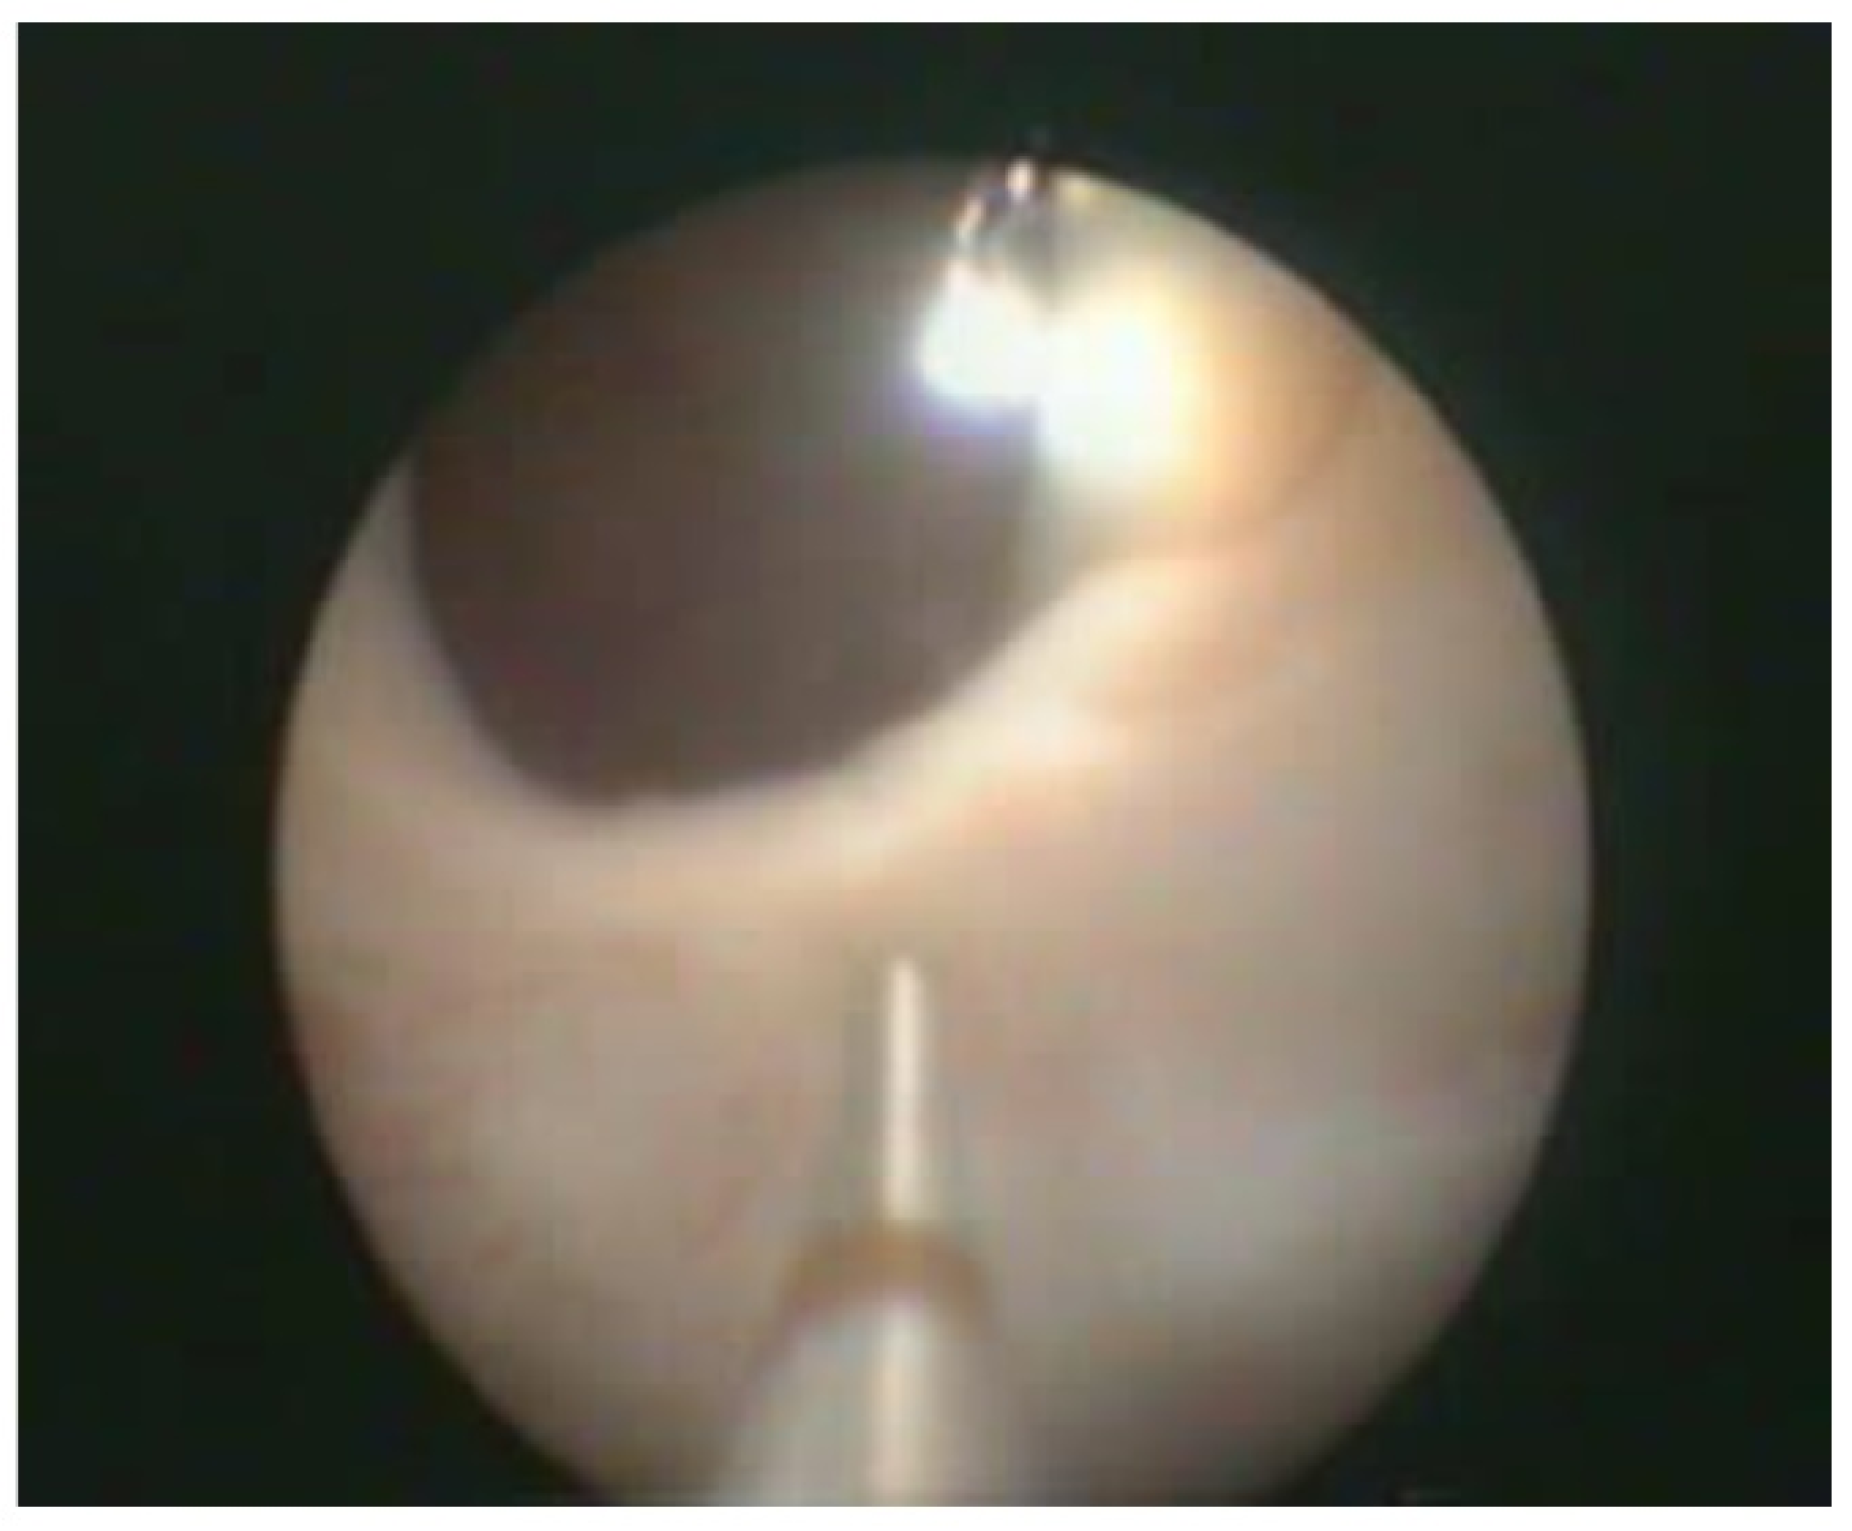

With the patient under general anesthesia in the lithotomy position, antegrade urethrocystoscopy was performed using a 9.5 Fr cystoscope (Figure 1). In parallel, percutaneous suprapubic bladder access introducing a second 9.5 Fr. cystoscope was accomplished. Four quadrant Dx/HA injections were performed, with the two surgeons guiding each other by parallel endoscopy to the optimal localization for injection (Figure 2, Figure 3 and Figure 4). In selected patients, the procedure was completed with transurethral intravesical Botox® injection. At the end of the procedure, a transurethral Foley catheter was placed and left in place for 10 days. Patients were discharged on the first day after surgery and they returned to the outpatient clinic for scheduled removal of the Foley catheter.

Figure 2.

Combined antegrade and retrograde endoscopy.

Figure 3.

Transurethral cystoscopy controlling the percutaneous suprapubic bladder access.